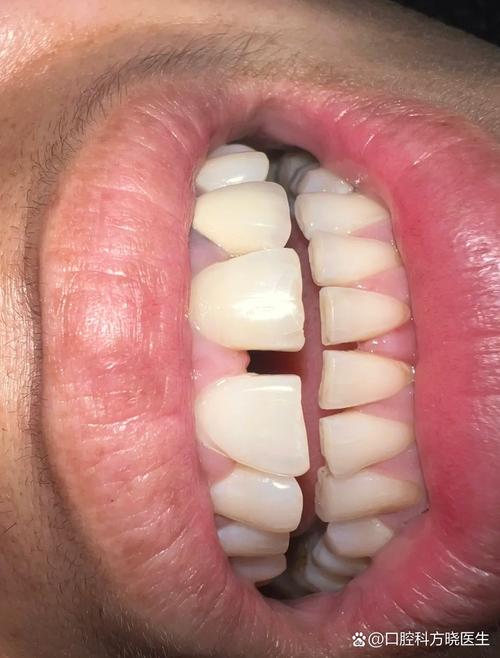

(图片来源网络,侵删)- 原因: 拔牙后未及时修复(种植、镶牙、活动假牙),邻牙会向缺隙倾斜移位,对颌牙伸长,导致邻牙与邻牙之间、邻牙与对颌牙之间出现牙缝。